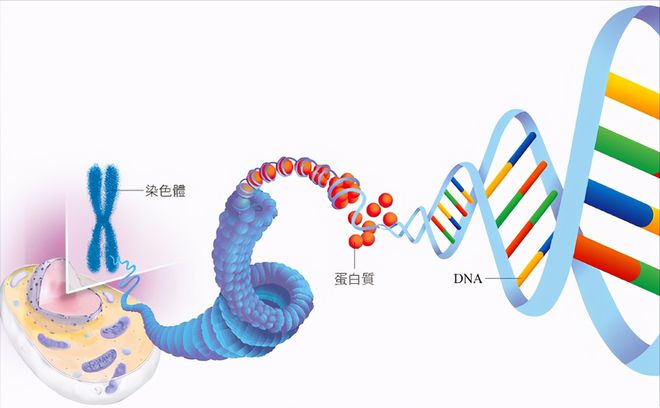

人类每个细胞 (精子和卵子细胞除外) 都有23对染色体,每一对染色体都是一条来自父亲,一条来自母亲。染色体上分布着许多的基因,掌管着我们身体所有的大小功能。

基因跟染色体一样也是“成对”的 (源自父方×1,母方×1)。跟染色体不同的是基因有“显性”及“隐性”之分。